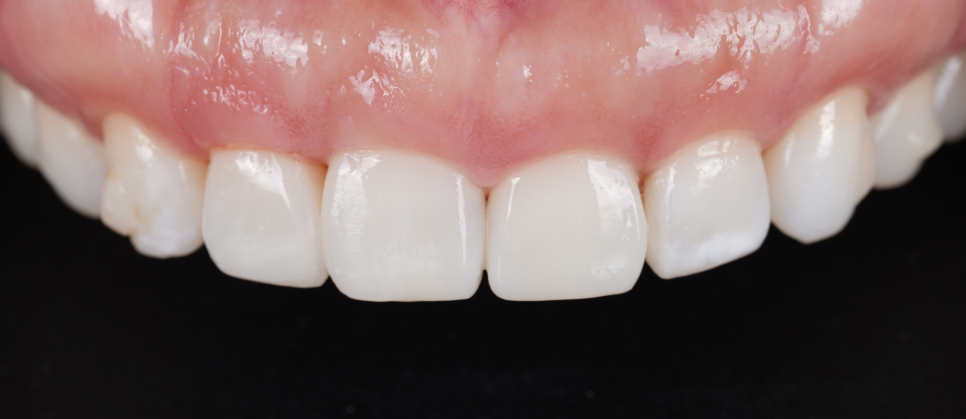

| ✅ 치아는 거의 삭제하지 않고, 기존 치아 형태에 맞춰 미세한 레진 레이어링 |

| ✅ 4개의 앞니에만 레진 수복을 진행해 정중선, 길이, 투명감, 회전된 느낌까지 자연스럽게 조율 |

| ✅ 밝은 색상을 사용하되 투명도가 살아 있도록 설계(미국 교정 문화 특유의 ‘하얀 미소’ 감성을 반영하되, 오버는 NO) |

촬영일 : 250714

“선생님, 진짜 너무 마음에 들어요.

이거 미국에서 하셨으면 완전 대박 나셨을 거예요!”

촬영일 : 250714 / 250714